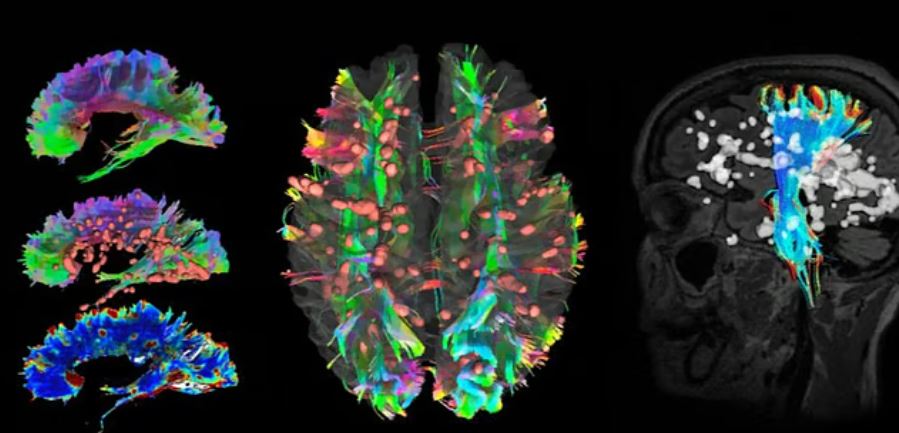

Главная разработка проекта — технология МРТ на основе ИИ, которая значительно улучшает точность и скорость диагностики рассеянного склероза. Особое внимание уделяется инструменту FLAIRstar, способному выявлять специфический биомаркер заболевания — «признак центральной вены».

Это открытие помогает врачам быстрее и точнее отличать рассеянный склероз от других неврологических заболеваний со схожими симптомами. Благодаря такому подходу сокращается время до начала лечения, что критически важно для пациентов.